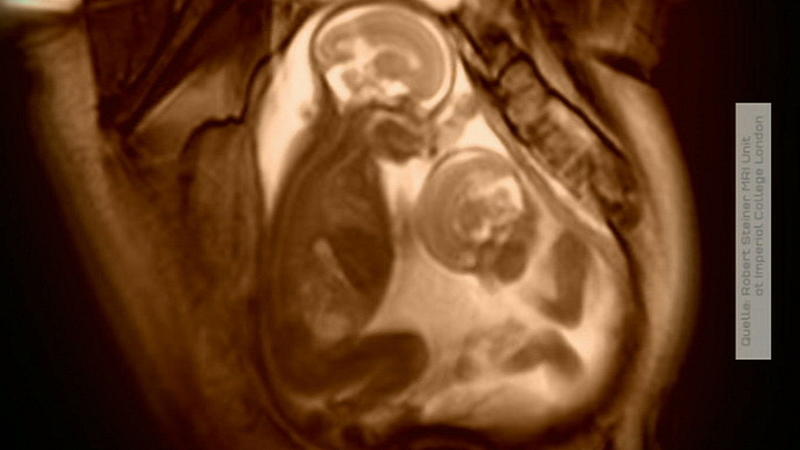

Häufiger als angenommen stirbt ein Embryo, der andere überlebt. Die möglichen Folgen für das überlebende Kind: gestörtes Bindungsverhalten und ein erhöhtes Risiko für angeborene Krankheiten Video: Zwillinge im Ultraschall.

Zwillinge sind was ganz besonderes. Live im Studio schauen wir per Schall auf diese beiden kleinen Wunder des ungeborenen Lebens Zwillinge sind zwei Geschwister.